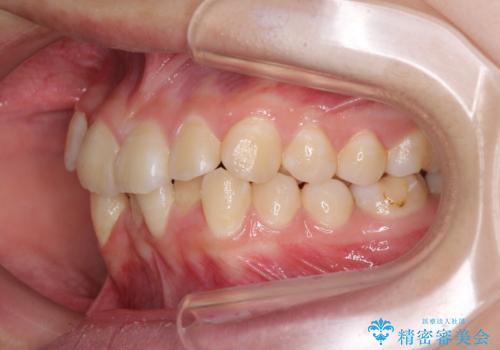

- 上下の八重歯と前歯のデコボコを気にして来院された患者様です。

右上の八重歯が特に著しく、上顎正中が右側にシフトしていました。

正中位置の改善に時間がかかることが予想され、2年半を治療期間の目標としておりましたが、20歳と年齢が若いこともあり、2年2ヶ月で治療を終えることができました。